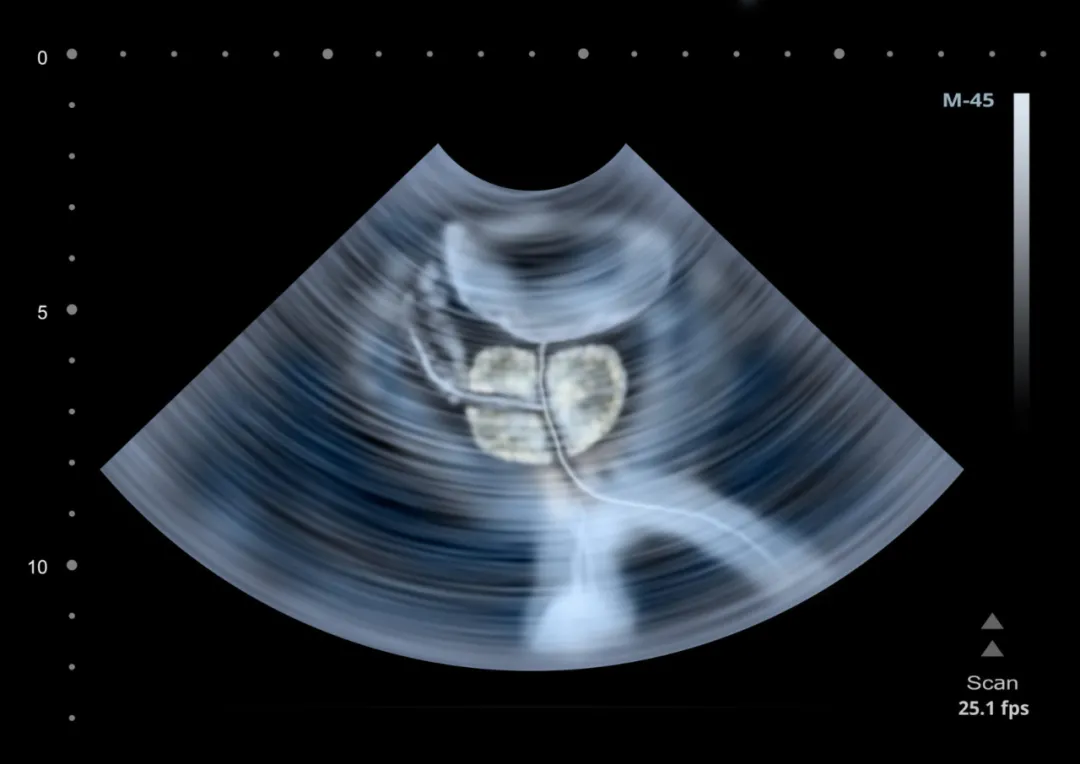

前列腺是影响男性健康的“重灾区”,增生、结石及钙化、囊肿都是常见的前列腺病变。

34.jpg